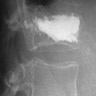

Θεραπεία της ασβεστοποιού τενοντίτιδος του ώμου (Barbotage)

Τεχνική:

Κάτω από τον έλεγχο των υπερήχων η της αξονικής τομογραφίας εντοπίζεται η ε

Κάτω από τον έλεγχο των υπερήχων η της αξονικής τομογραφίας εντοπίζεται η επασβέστωσ